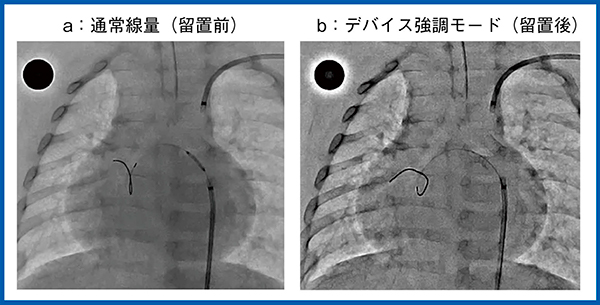

近年,動脈管開存症においては,動脈管に冠動脈ステント留置を行い,プロスタグランジン合成阻害薬の投与を止める例が増えている。図4は,心室中隔欠損を伴う肺動脈閉鎖症を合併した動脈管開存症で,左の肺動脈に血流が供給されている。冠動脈ステントの留置前後の画像を比較すると,デバイス強調モード(図4 b)ではワイヤやデバイスが明瞭であり,デバイス留置時の安全性の向上に寄与する。さらに,本症例は下行大動脈から起始する体肺動脈側副血行路(MAPCA)にも冠動脈ステントを留置しているが(図5),デバイス強調モード(b)では,ステントのwaistが完全に取れていない状況もしっかりと確認できる。

図4 デバイス強調モード:肺動脈への冠動脈ステント留置